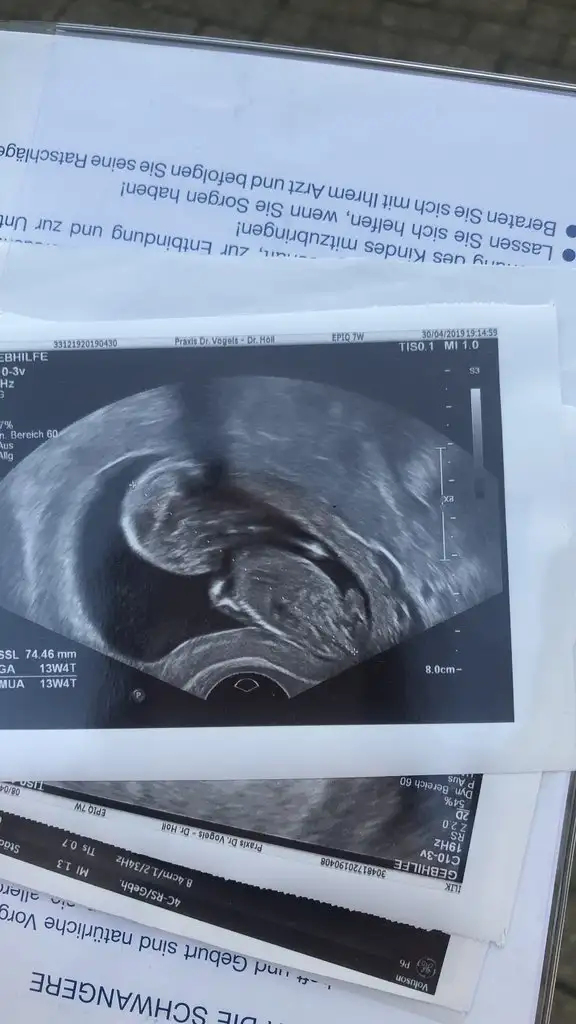

Kızlar 2li haftaya kaldı. Cinsiyet kesin olmamakla beraber pipi görünmedi![]()

ay esniyor mu o sankiiiKızlar 2li haftaya kaldı. Cinsiyet kesin olmamakla beraber pipi görünmedi![]()